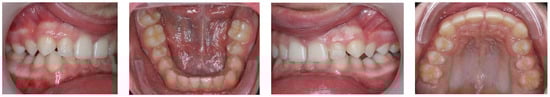

2.1. Diagnosis and Etiology

2.2. Treatment Objectives

4. Discussion